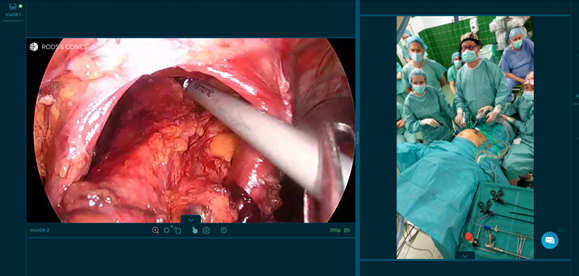

Po raz pierwszy w historii Rydygiera, zabieg przeprowadzany na szpitalnym bloku operacyjnym w Nowej Hucie transmitowany był w czasie rzeczywistym do ośrodków medycznych w 15 krajach Europy oraz do 4 szpitali w Polsce.

Skomplikowaną operację lewostronnej hemikolektomii, której poddany został 68 letni Pacjent z nowotworem odbytnicy, wykonywał i komentował dla obserwatorów prof. Andrzej Budzyński, Ordynator Oddziału Chirurgii Ogólnej i Onkologicznej Szpitala Rydygiera, w asyście 3 osobowego zespołu szpitalnych operatorów.

Tę strategię docenili uczestnicy warsztatów, obserwujący ponad 3,5 godzinną operację prowadzoną przez prof. Budzyńskiego, którzy dzięki transmisji live surgery mieli możliwość zadawania pytań, a tym samym zyskali szansę teoretycznego współtworzenia koncepcji dla kolejnych etapów prowadzonego zabiegu.